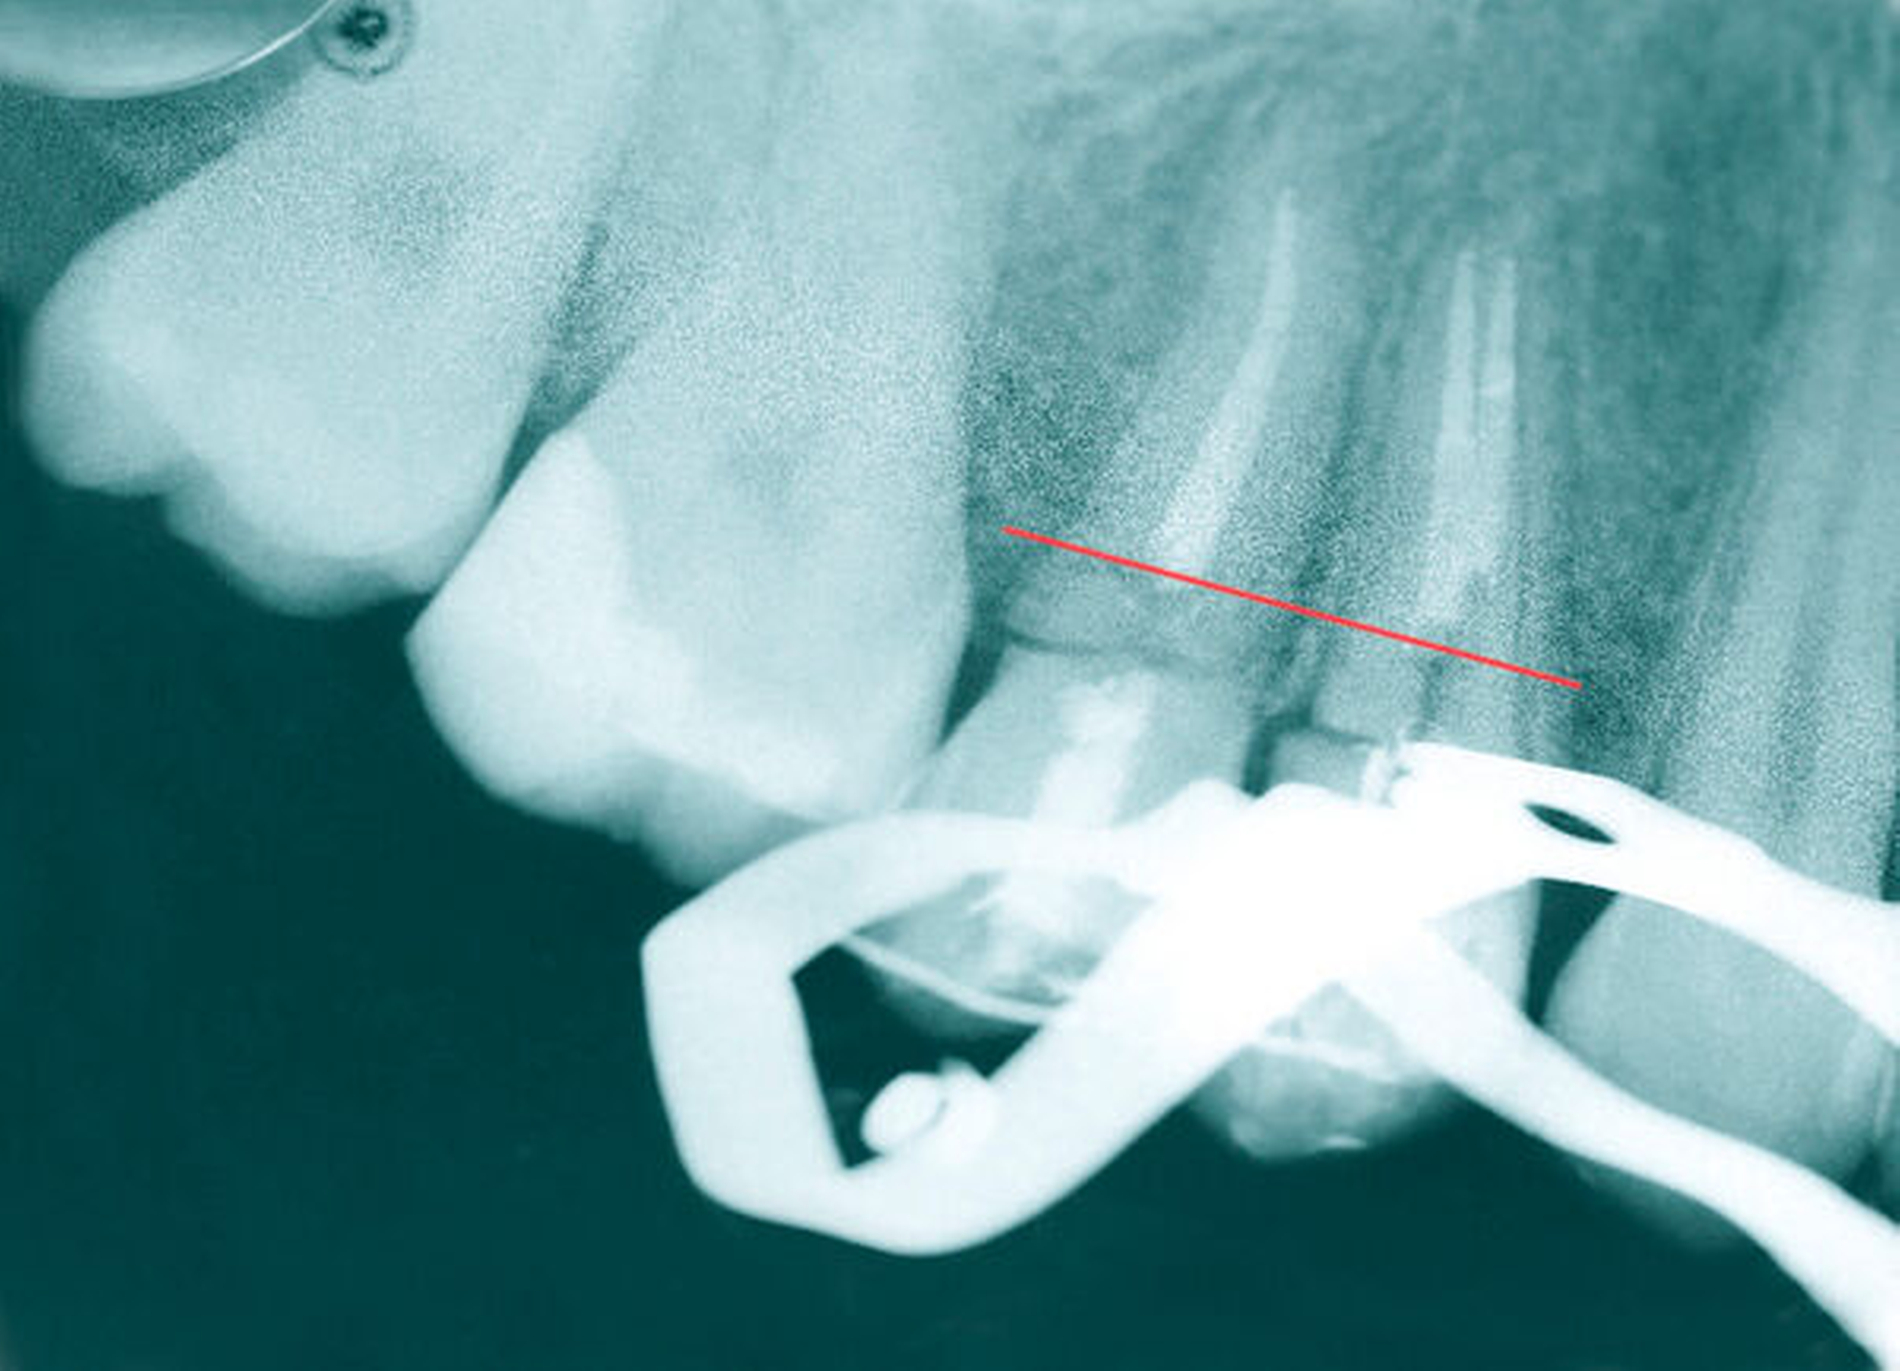

Der extraorale Befund war bis auf ein Hämatom im Kinnbereich unauffällig. Eine Kiefergelenksfraktur wurde bereits am Vortag im unmittelbar nach dem Unfall aufgesuchten Klinikum Ludwigshafen ausgeschlossen. Intraoral zeigte sich ein vollständiges, kariesfreies Gebiss mit Z. n. abgeschlossener kieferorthopädischer Therapie. Die Zähne 14 und 15 hatten einen Lockerungsgrad II sowie eine alio loco angebrachte flexible SÄT-Drahtschienung. An den Zähnen 16, 26, 45 und 46 wies die Patientin z. T. ausgedehnte Schmelz-Dentin-Abscherungen auf. Nach Entfernung der Schienung 14 Tage später zeigten sich die komplizierten Kronen-Wurzel-Frakturen an 14 und 15.

Nach gründlicher Aufklärung und Beratung der Patientin und ihres Vaters wurde zunächst die Füllungstherapie der Zähne mit Schmelz-Dentin-Frakturen sowie die Mikroskop- gestützte endodontische Behandlung der beiden Prämolaren durchgeführt. Hierfür wurden die mobilen vestibulären und oralen – lediglich an der Gingiva gestielten – Zahnfragmente an 14 und 15 zunächst belassen, um eine möglichst gute Trockenlegung zu erreichen, da diese Fragmente sich mithilfe der Kofferdamklammer so gut adaptieren ließen, dass eine ausreichend gute Trockenlegung ermöglicht wurde.

Nach der endodontischen Behandlung der Zähne 14 und 15 erfolgte die chirurgische Entfernung des mobilen vestibulären beziehungsweise oralen Kronenfragments sowie der infragingival frakturierten Wurzelanteile. In der gleichen Sitzung erfolgte die Aufklappung vestibulär und oral, um nach Trocknung der Zahnstümpfe eine adhäsive Befestigung von zuvor auf dem Modell gefertigten Drahtschlaufen (018``Stahl: Dentalline, Deutschland) zu ermöglichen. Diese wurden mittels dual härtendem Composit (Rebilda DC, Voco) intrakanalär verankert. Mithilfe eines weiteren, an den mesialen und distalen Nachbarzähnen adhäsiv angebrachten Drahtes (17x25 TWIST, 3-fach verseilt; Dentalline, Deutschland) und einer elastomeren Kette (Energy Chain, Rocky Mountain Orthodontics, USA) war es nun möglich, die Wurzelreste orthodontisch aus den Alveolen zu extrudieren. Hierzu waren über einen längeren Zeitraum mehrere Behandlungstermine nötig, bei denen die Gummizüge entsprechend des Behandlungsfortschritts gewechselt wurden. Des Weiteren erfolgten in regelmäßigen Abständen Inzisionen im PA-Spalt, um eine Mitwanderung des Knochens zu vermeiden. Anders als bei festsitzenden Multibandapparaturen ist eine definitive Kraftangabe bezüglich der Extrusion nicht möglich, da sich die Kräfte mit fortschreitendem Extrusionsgrad und je nach verwendeter elastomerer Kette ändern.